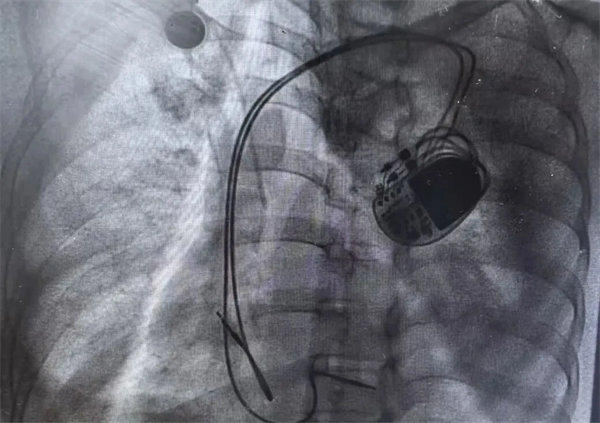

在充分术前准备和家属的理解支持下,心血管内一科主任翟向伟副主任医师、陈万林副主任医师及介入导管室团队为患者实施了双腔心脏永久性起搏器植入术。通过左侧腋静脉入路,精准、轻柔操作顺利植入起搏器。术后经过医护团队的精细诊治,起搏器囊袋如期愈合,患者可自由活动,生活质量得到有效改善。患者及家属露出了久违的笑容。